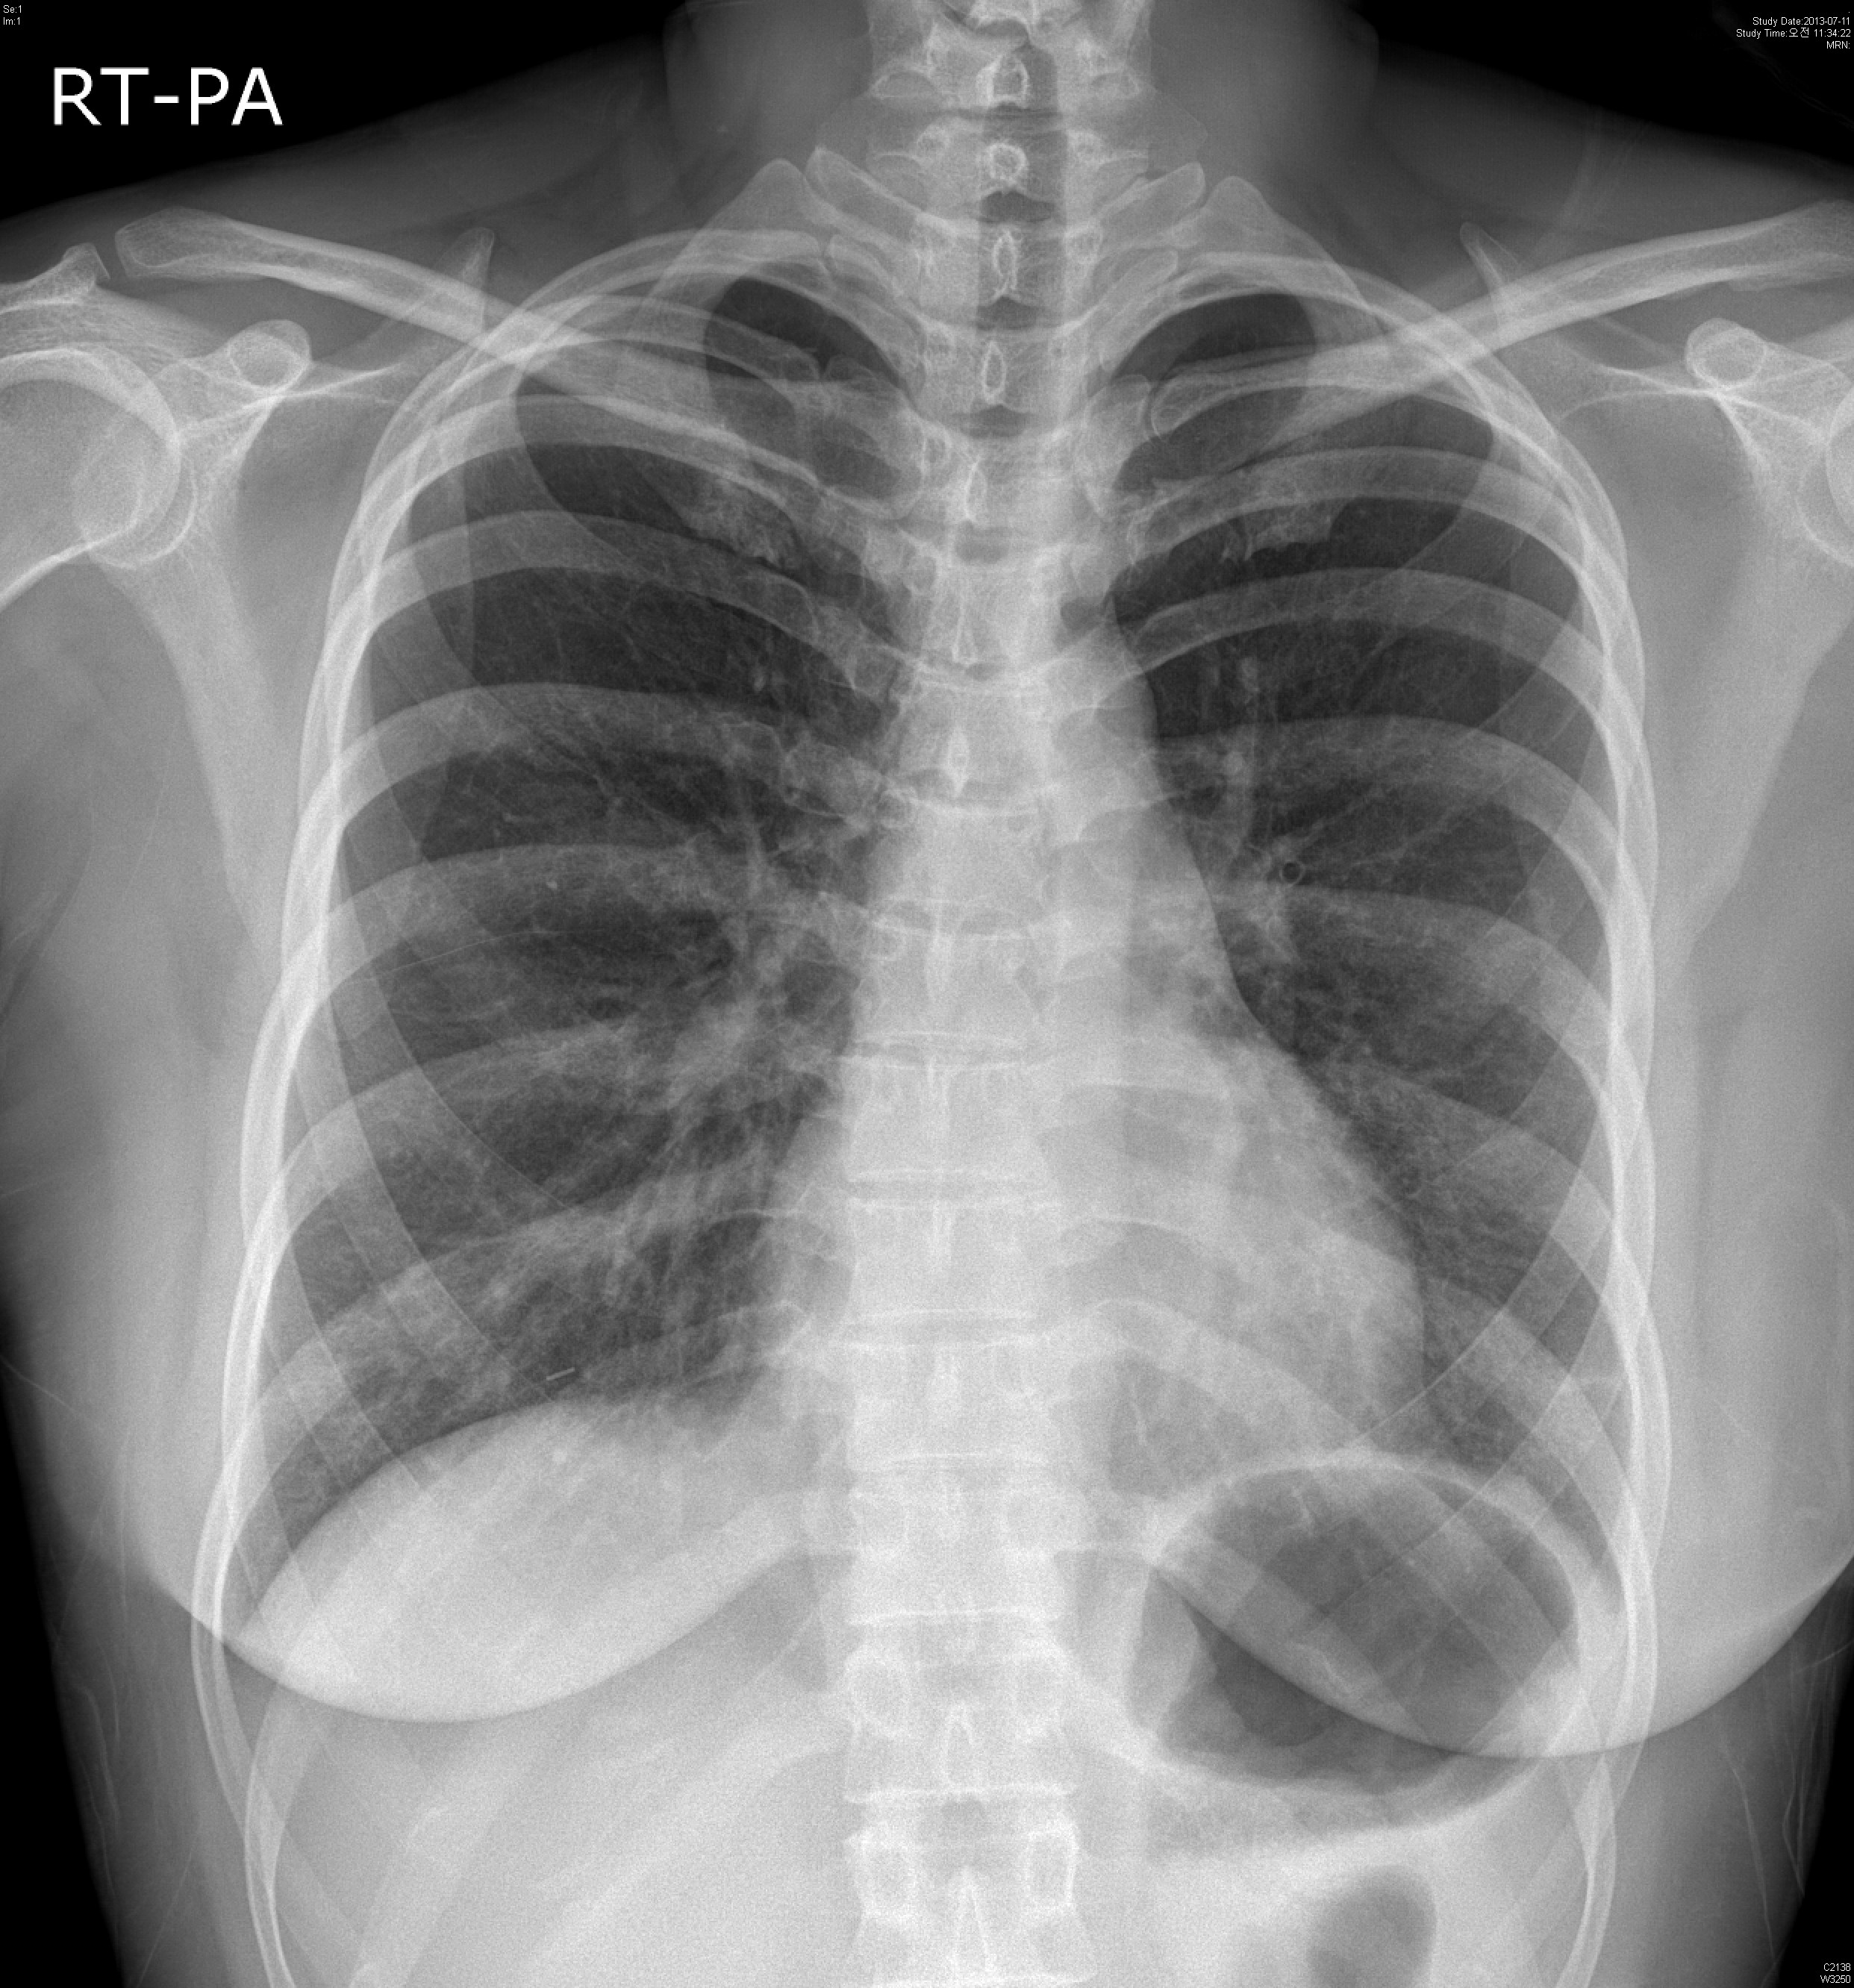

39¿©ÀÚ È¯ÀÚ·Î, Rt breast cancer Áø´ÜÇÏ¿¡ 2013³â 3¿ùºÎÅÍ Ç×¾Ï Ä¡·á ¹ÞÀº ȯÀÚ·Î,

dyspnea on exertion ¾ÇÈ­µÇ¾î È£Èí±â³»°ú ¹æ¹®ÇÔ.

CRP 0.68 mg/l, Procalcitonin<0.05 mg/dl

CBC: 6000-12.1-246k(neutrophil:71.8%, eosinophil 1.0%)

PFT: FVC/FEV1/Ratio: 2140(56%)/ 1810(60%)/ 84% (3ÃÊ ÀÌ»ó ºÒÁö ¸øÇÔ)

Bronchodialtor response (-)